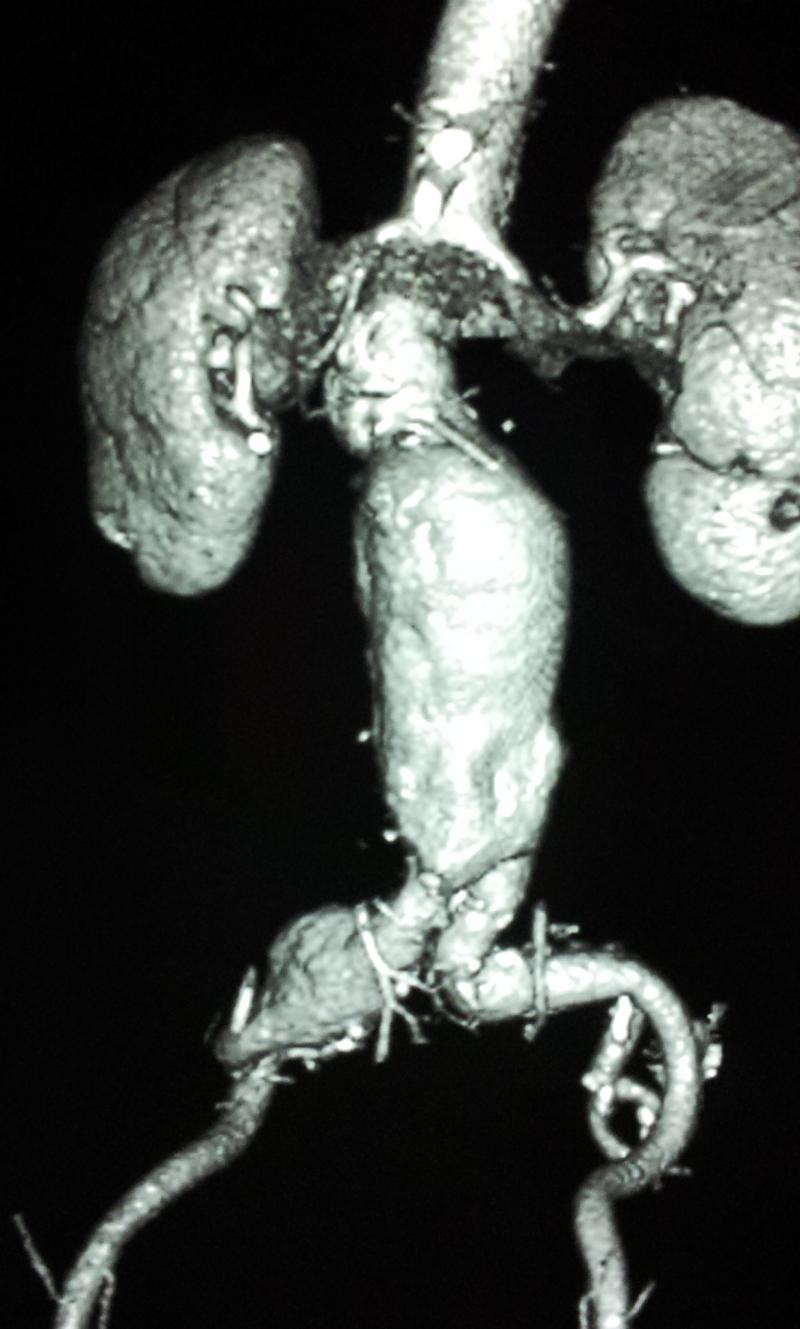

Recently, (October 2016) we have been able to perform total aortic debranching of the thoraco-abdominal aorta and then perform an EVAR . In this case, the complete branches to the abdominal organs were bypassed from bilateral iliac arteries. The arteries bypassed were the Coeliac, superior mesenteric, left hepatic, abberant right hepatic artery and both renal arteries. This is termed as Aortic debranching operation.The patient is doing well

The above is the aneurysm and below is the scan after repair